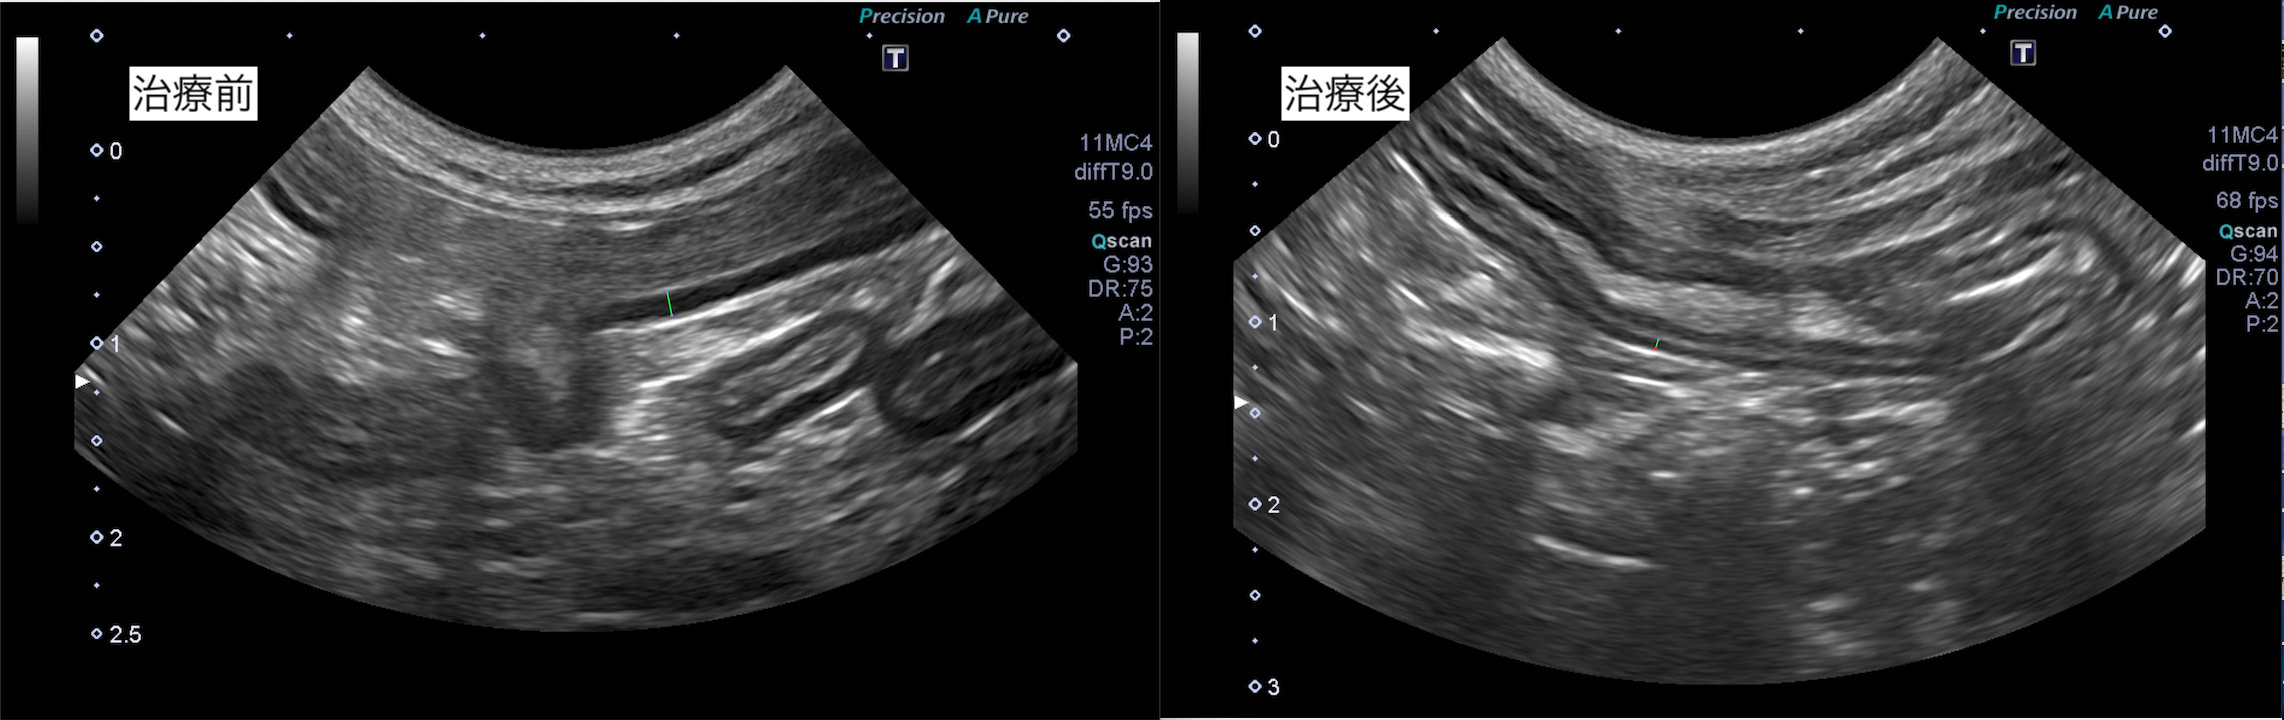

超音波検査では、消化管の構造の一部肥厚が認められました。

また超音波検査でも粘膜の肥厚は改善傾向です。